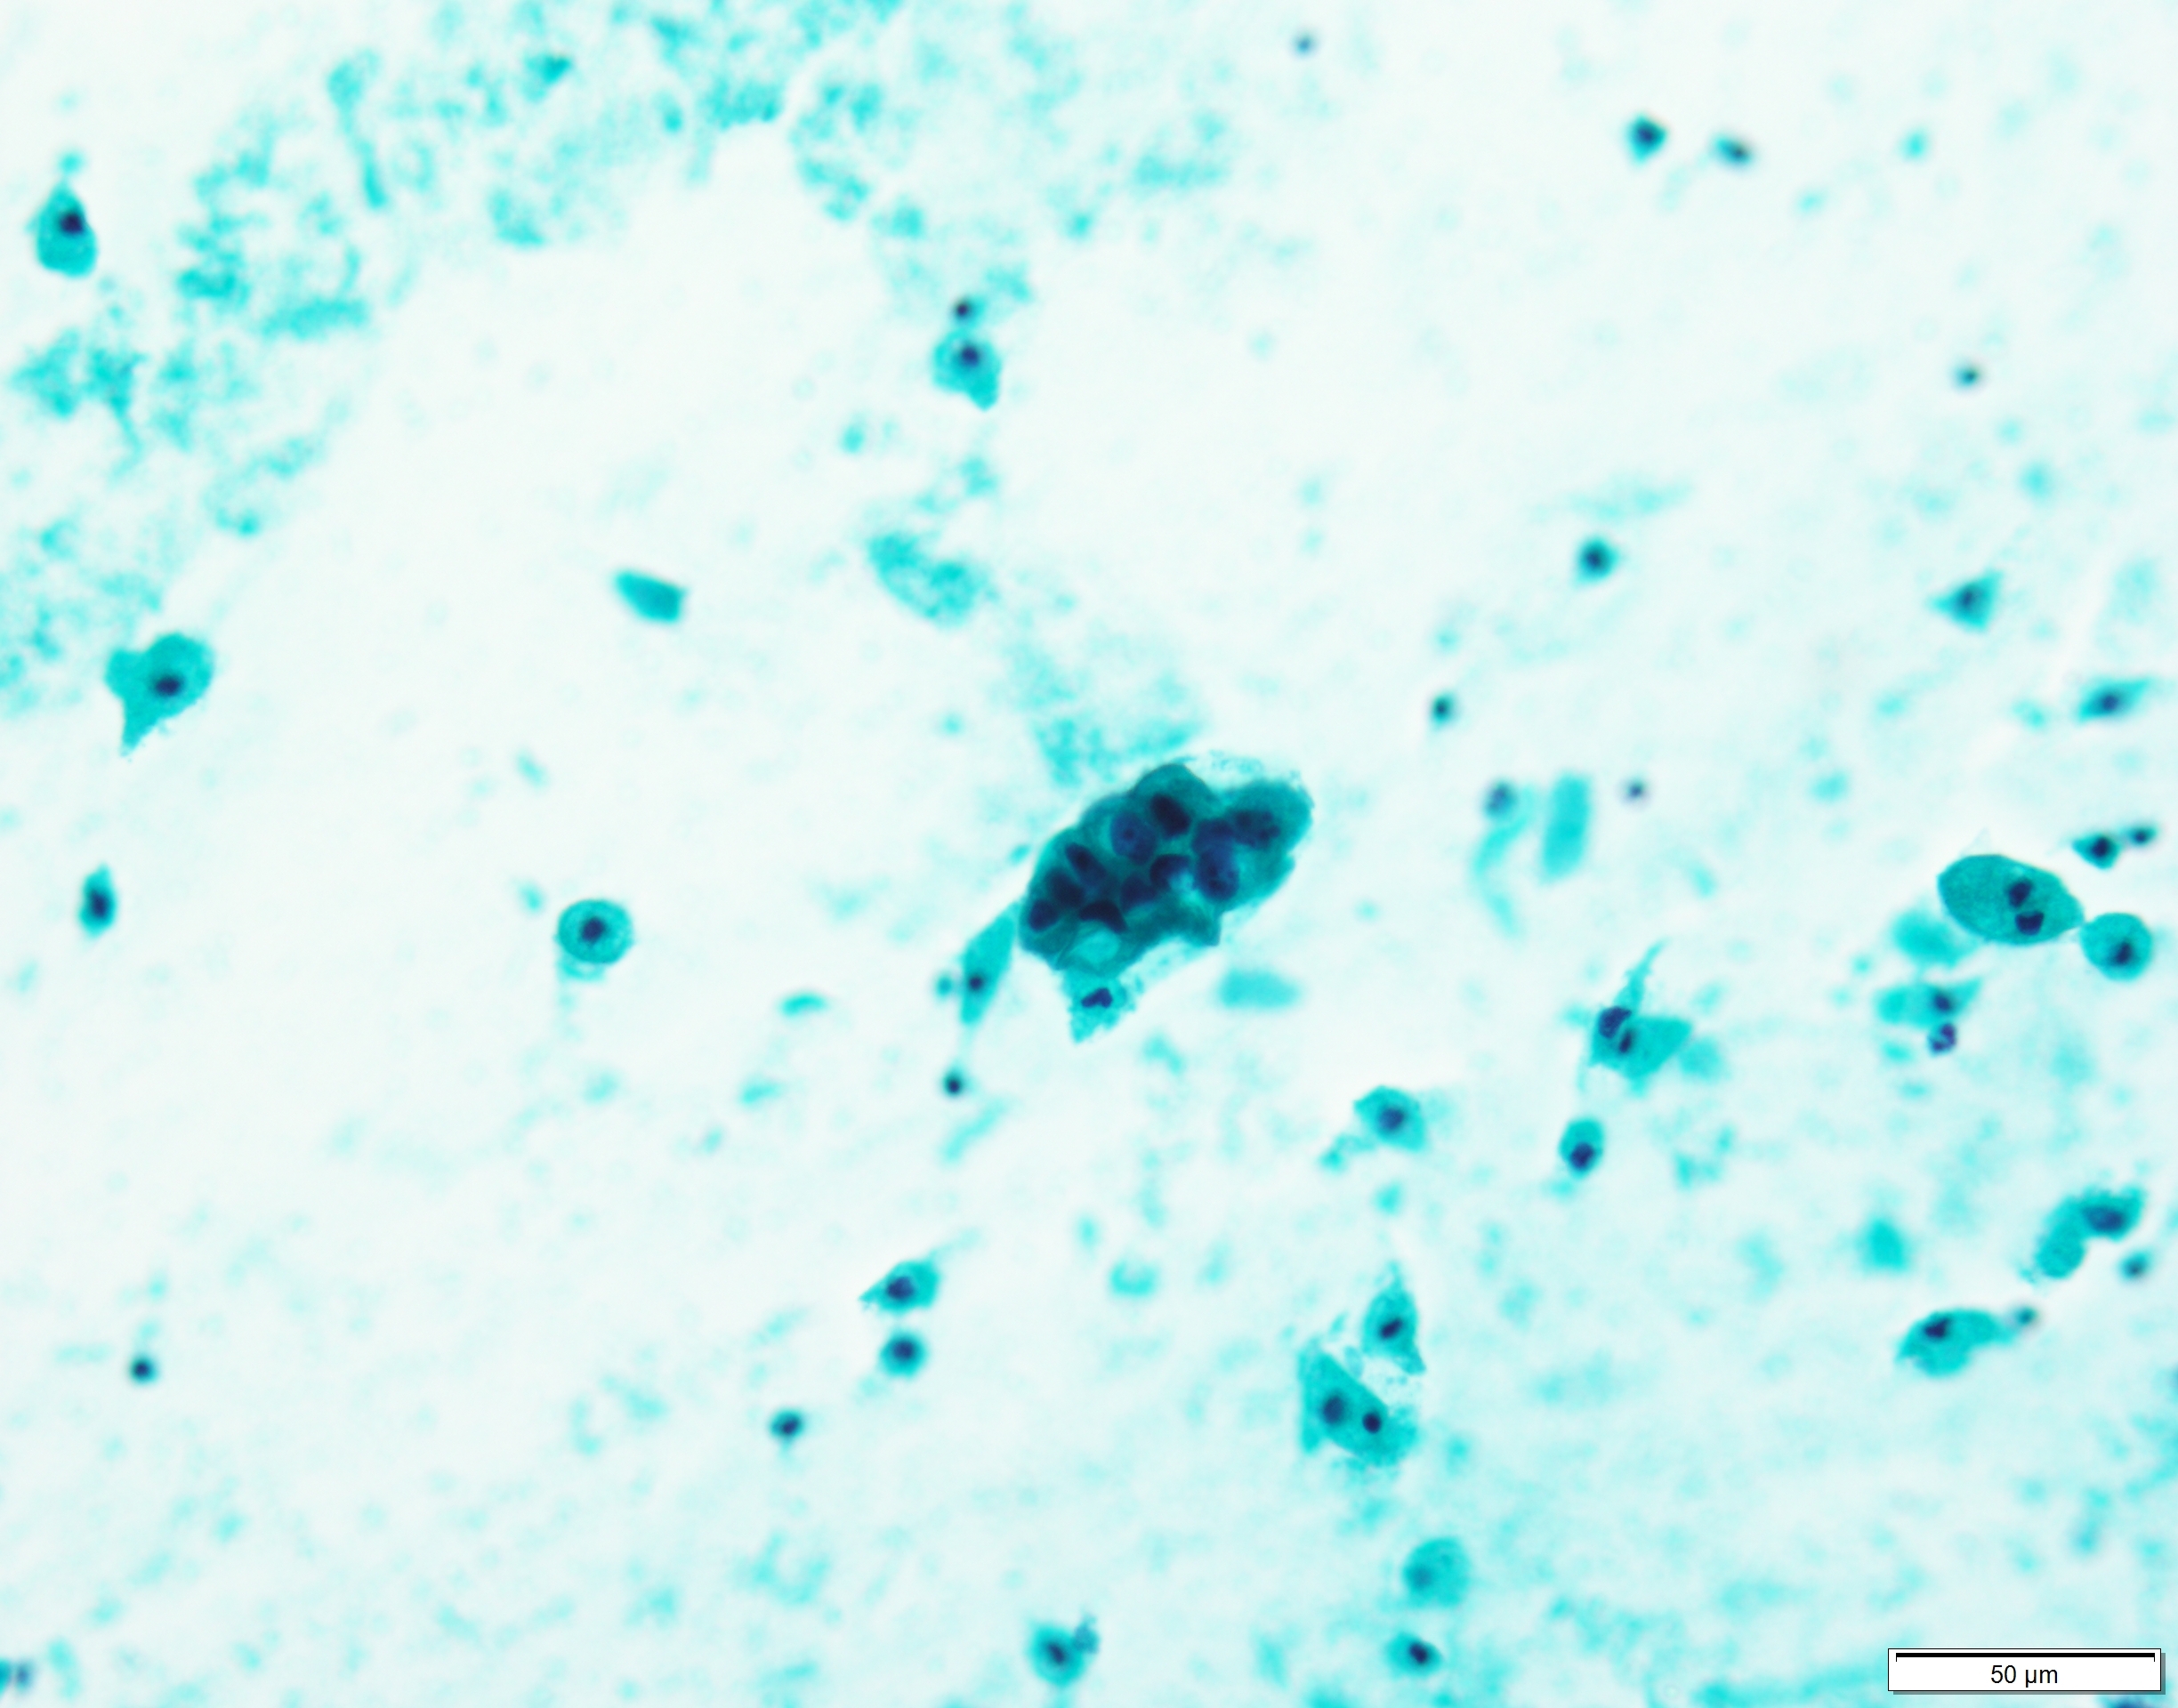

Pap×40